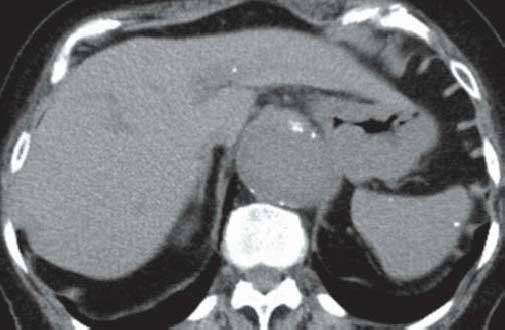

男性,48岁,以肺结节就诊。

A

B

图A和B为轴位CT平扫,示肝、脾内多发大小不一的钙化,肝、脾大小形态正常,图C和D为冠位重组纵隔窗及肺窗,示纵隔、肺门淋巴结钙化及肺的钙化结节,同时发现主动脉瘤。

组织胞楽菌病是美国中部的一种地方病,自艾滋病流行以来,本病发病率明显上升,在非流行地区也有报道。大多数组织胞浆菌病患者伴有纵隔淋巴结肿大、钙化(如本例所示),可引起纵隔压迫症状。患者腹部CT扫描可见散布的组织胞浆菌病,肝大(63%)、脾大(38%)、弥漫性脾密度减低(19%)、双侧肾上腺肿大、淋巴结肿大(44%)。在美国,治愈的组织胞浆菌荚膜感染是引起弥漫性脾钙化的最常见原因,引起多发脾钙化的其他原因有治愈的结核、布鲁杆菌病及肺囊虫感染、血管瘤、静脉石、含铁血黄素沉着症、镰状红细胞贫血和含铁结节(G-G小体)。